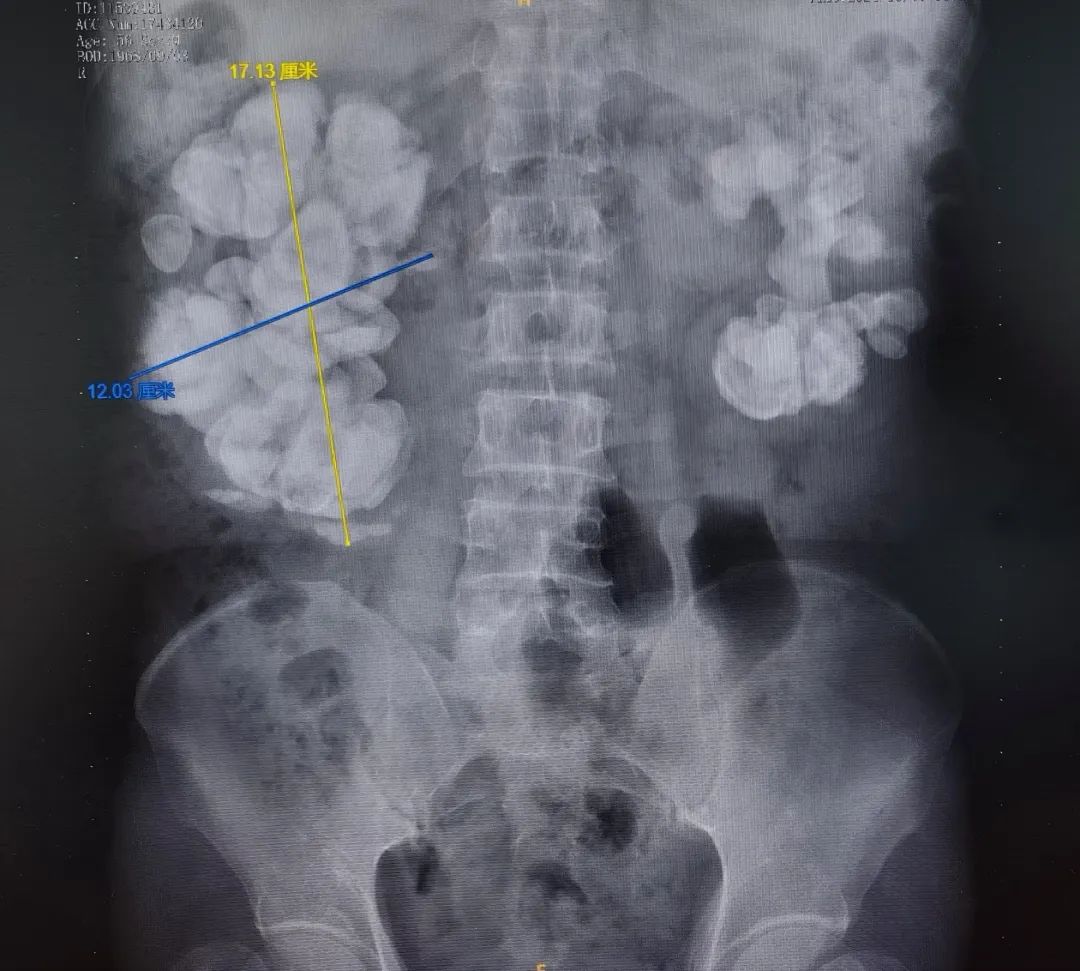

影像片子上

患者的双侧肾脏

尤其是右肾里

赫然矗立着一座"巨石阵"

鹿角形肾结石

不仅霸占了整个肾脏空间

还嚣张地蔓延生长成了

17cm×12cm"大个"

泌尿外科主诊医师刘宇保接诊后查看患者影像资料,CT示双侧肾脏复杂性巨大肾结石,右肾尤为严重,平均最高CT值达1100-1300HU(代表结石硬度,相当于各种不同结石成分中最坚硬的一类),血肌酐在240μmol/L左右(正常值为<82~95μmol/L),处于肾功能不全代偿期。种种因素导致微创手术治疗难度极大,但患者右侧肾脏功能仍有30%-40%。患者刚50出头,是全家收入来源的主要劳动力,保肾的意愿尤其强烈。切除一侧肾脏,会影响患者另一侧肾脏的代偿能力,若左侧肾脏在手术以后出现结石复发、严重感染等问题,将严重影响到其生活质量。在科室主任李建兴的带领下,以微创取石作为最后的选择,刘宇保和患者一起先行尝试"保肾大作战"方案。

巨石阵体量惊人:右肾这颗鹿角形结石已经让肾脏膨胀到正常的3倍大。